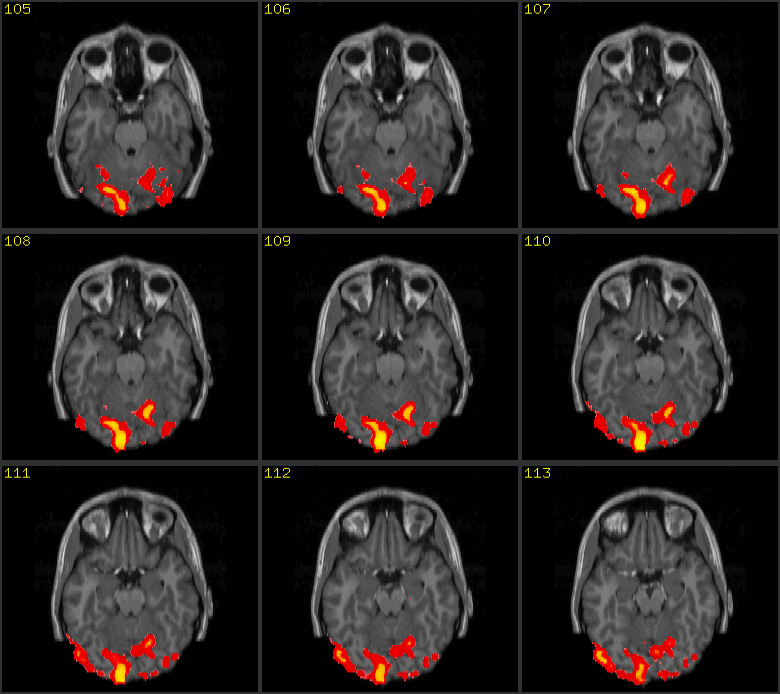

The automatism and, at the same time,

ineffability of thinking can be put into an image thanks to progresses in

neuroscience and biomedical techniques of image formation and visualization.

The illustration shows two images: the first one is a scan of the brain

obtained with Magnetic Resonance Imaging (MRI), the second is its functional

version (fMRI). MRI is a non-invasive scientific technique that generates

images of the body for diagnostic and research purposes. Along with its

functional version, MRI has been extensively applied to studies of brain

anatomy and cognitive functions, enabling researchers to detect and measure

the neuronal activity in almost real time. By showing the human brain at work,

brain scans are presented in the wider public arena and, specially, in the

media, as evidence of conditions of normality or illness that prompt us to

reshape our concept of personal identity (Dumit 2004).14

Brain scans embody both image traditions

that historian of science Peter Galison individuated within the field of

physics: the first tradition, called logical, substitutes the notion of the

image with the notion of statistical projection of data and digital

information; the second tradition, called image, describes images as natural,

illusionary or mimetic. According to this second tradition, images ‘preserve the form of things as

they occur in the world’ (Galison, 1997, 807). Brain scans function as authoritative

visual objects that are part of a multi-layered ensemble of networked

techniques and technologies (both analogical and digital) and human mediations,

embodying the logic of the database (de Rijcke and Beaulieu, 2014) and being

more the statistical projections of data rather than representations.

Therefore, brain scans can be aptly called image-data.

Experts in the laboratory do not always need to see the image because they are capable of reading it in accordance with the aforementioned logical tradition. Non-experts, on the contrary, can interpret the brain scan only as an image belonging to the second tradition. Both strategies, reading and seeing, however, are made possible thanks to notions that belong to art history and practice such as perspective, background and foreground, chiaroscuro, intensity, orientation, composition, colour grading, etc, and by bearing upon the cultural history of the representations of the brain from Leonardo, Vesalius through phrenology and recent brain imaging techniques. Already at a production stage brain scans are created by referring to the cultural background, concepts and techniques that belong to the art field as Elkins highlights: ‘the images cannot be produced without drawing on the longer history of mimetic art. For that reason they also cannot be fully interpreted without fully tracing the effects of modern and pre-modern pictures…they are art images in disguise’ (Elkins, 2008: 173). This double belonging of brain images to the scientific and the artistic field is in tune with de Rijcke and Beaulieu’s understanding of brain scans as boundary objects between disciplines (de Rijcke and Beaulieu, 2014: 131) and with our attempt to discuss brain scans along with an image coming from experimental cinema.

This series of images can be seen but cannot be read without knowing the language of neuroscience and of brain anatomy and physiology. For the purpose of this essay, it is not worthwhile going into details on how brain scans are produced, re-mediated and interpreted inside and outside the laboratory. Therefore, I shall not discuss the scholarly literature (de Rijcke and Beaulieu, 2014; Prasad, 2005; Alac, 2008; Dumit, 2004 to name just a few) that shows how brain images are the result of complex socio, technical and semiotic procedures of mediations and interpretation taking place inside the laboratory and among different professionals.

I am more interested in juxtaposing two procedures of creating and approaching images, the one followed by Godard and the one followed by those who obtain and read brain scans with the help of biomedical imaging, to see how these two procedures let images guide us, let images function as arguments. As we have seen, Godard adopts a technique of montage (the anti-montage) within a single still image. He moves horizontally on the surface of the image, framing different parts of the picture, focusing on fragments, on small details in close-up. He deconstructs, anatomically, the original photograph in a series of images that bear meaning on their own but whose meaning, at the same time, changes when each fragment is re-assembled to form the original picture. Godard treats the image as a series of layered elements that are not purely visual (we should remember that words superimposed on screen count as images too in Godard) and that can be put in relation one with another. In Godard the different layered images (sound, image, text) are worked separately and then put back together. On the opposite, the reading enacted on a brain scan is a surface scanning, but layers are piled up vertically, they are added onto the image for the single snapshot alone does not make sense. It is the ensemble of layered scans that constitutes the image.

The brain image simultaneously works for and against our reading, whether it refers to the logical, informational element of the image (the image-data) or to the pictorial element (background and foreground, shades of grey or different colours and perspective). Unable to read MRI images, as non expert viewers we scan over their surfaces and attempt to solve their ambiguity. The result is the perception of potential and hidden images in brain images, a perceptual automatism enacted by analogical and metaphorical thinking. As art historian Dario Gamboni defines them, potential images are those that: “are established - in the realm of the virtual - by the artist but dependent on the beholder for their realization, and their property is to make the beholder aware - either painfully or enjoyably - of the active, subjective nature of seeing” (Gamboni, 2002: 18).

However, the revealed potential image (which is often an archetype) might be as puzzling as the image that conceals it. Potential images hidden in MRI and fMRI scans are emblematic of our uneasiness and anxiety in front of images, especially in the case of non representational images. Elkins suggests that our anxiety forces us to find hidden images in order to explain what puzzles us in certain ones. He highlights how once we see a hidden image, we cannot avoid seeing the same form and interpreting the entire image, which concealed the hidden one, in like manner (Elkins, 1999). Therefore hidden images function like viruses.

To stop the proliferation of viral potential images, one is forced to understand the process of formation of a sequence of brain scans. The most important thing to notice is that MRI maps a previously framed area of the body – that is, an area that is already transformed into an image. The procedure of creating MRI images using mathematical functions of transformation is an action incised onto the image rather than onto the object to imagine (for instance, a part of the brain). MRI images are not photographic snapshots of the brain. Rather, they are reconstructed out of a grid-like modular and repetitive structure (the k-space, a virtual space where the digitized magnetic resonance signals are stored during data acquisition). At the end of the scan, the data are processed with algorithms and the final image is created.